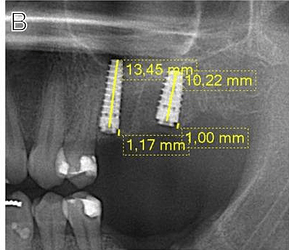

Case photos below provided by Rehberger Bescós F, Salgado Peralvo ÁO, Chamorro Petronacci CM, Chele D, Camacho Alonso F, Peñarrocha Oltra D, Lado Baleato Ó, Pérez Sayáns M. [Marginal bone loss and associated factors in immediate dental implants: a retrospective clinical study.](Marginal bone loss and associated factors in immediate dental implants: a retrospective clinical study - PMC)

Measurements for the calculation of the MBL performed: A Preoperative evaluation; B immediate postoperative period; C 2 months after placement of the implants; D 36 month follow-up